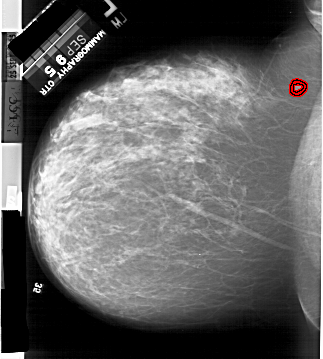

A_1899_1.LEFT_CC

LEFT_CC LINES 6091 PIXELS_PER_LINE 5491 BITS_PER_PIXEL 12 RESOLUTION 43.5 OVERLAY

FILE: A_1899_1.LEFT_CC.OVERLAY

TOTAL_ABNORMALITIES 1

ABNORMALITY 1

LESION_TYPE MASS SHAPE IRREGULAR MARGINS SPICULATED

ASSESSMENT 5

SUBTLETY 4

PATHOLOGY MALIGNANT

TOTAL_OUTLINES 2